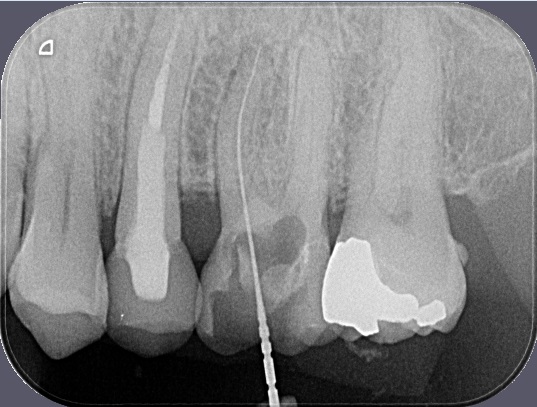

Porovnání průměrného ošetření způsobem plně hrazeným ze zdravotního pojištění (obrázek vlevo) a ošetření způsobem nadstandardním (obrázek téhož zubu po přeléčení vpravo) mohou přinést rentgenologické snímky níže.